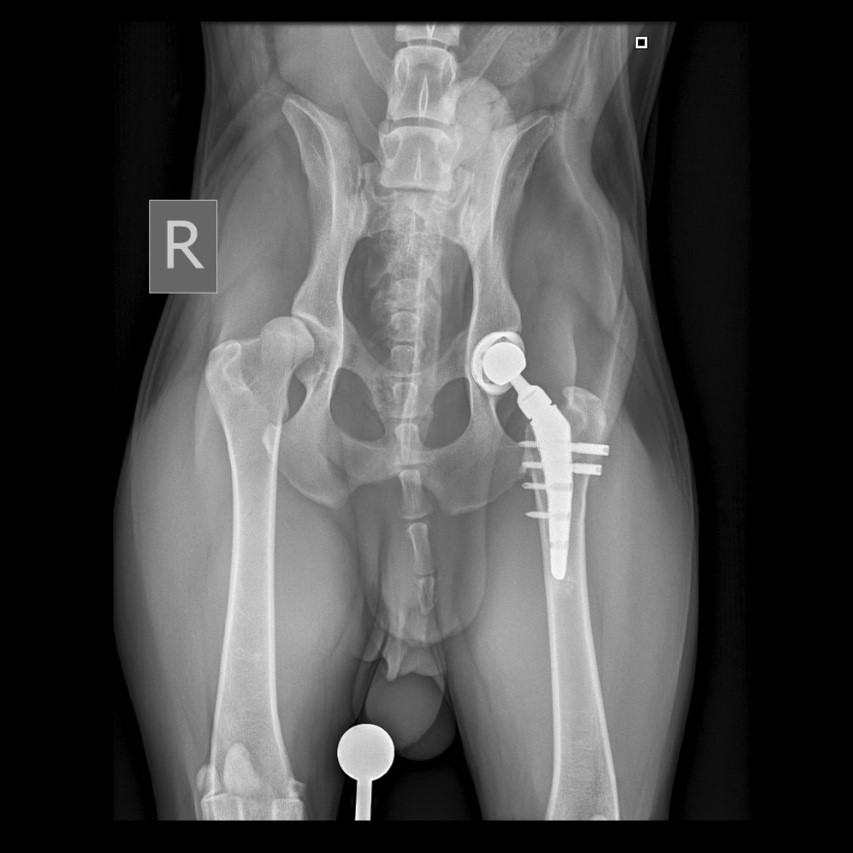

На основании неврологического осмотра не было выявлено патологических изменений. По результатам ортопедического осмотра правого и левого тазобедренных суставов: ограничение диапазона движений, крепитация, болезненность при манипуляциях; другие суставы без особенностей.Была проведена рентгенография тазобедренных суставов в дорсовентральной проекции с экстензией тазовых конечностей (фото 1).

Было рекомендовано и проведено хирургическое лечение – протезирование тазобедренных суставов с интервалом между операциями в 3 месяца (фото 4).

После завершения операции выполняется серия контрольных рентгенограмм для оценки положения имплантатов (фото 4, 5).

При остеоартрите объективным доказательством наличия хронической боли может служить снижение мышечной массы больной конечности (фото 4). При односторонних состояниях это можно проверить посредством ее сравнения с мышечной массой здоровой конечности. В билатеральных случаях, например при дисплазии тазобедренных суставов, наблюдается общее снижение мышечного тонуса в мышцах тазовых конечностей6.